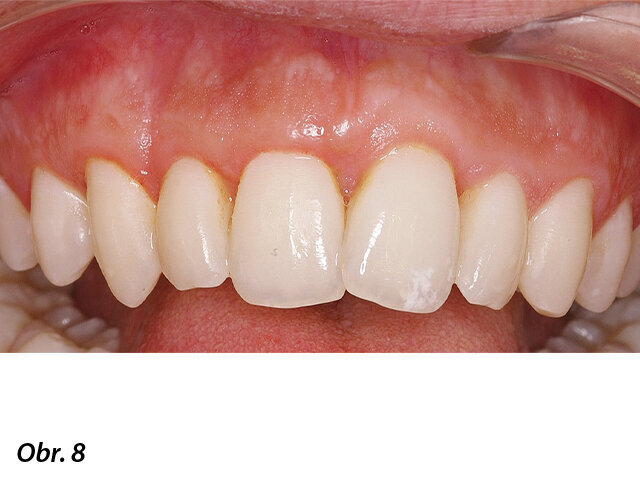

Zhojená a esteticky konsolidovaná oblast.